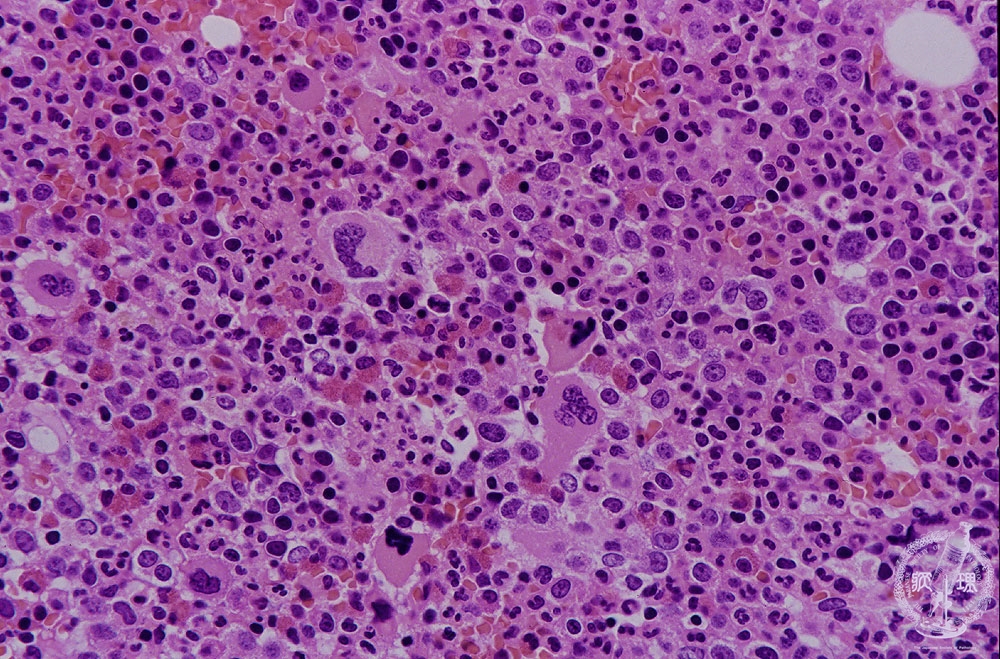

Microscopic image (H&E high power view): In the marrow granulocytic and megakaryocytic precursors proliferate as well as the erythroid progenitors. However, the blast cells do not proliferate. Thrombocytosis and granulocytosis are often accompanied. Polythythemia vera, one of the myeloproliferative disorders, transforms to primary myelofibrosis. The picture of the marrow resembles that of chronic myeloid leukemia, however microscopic features of peripheral blood smear are different.